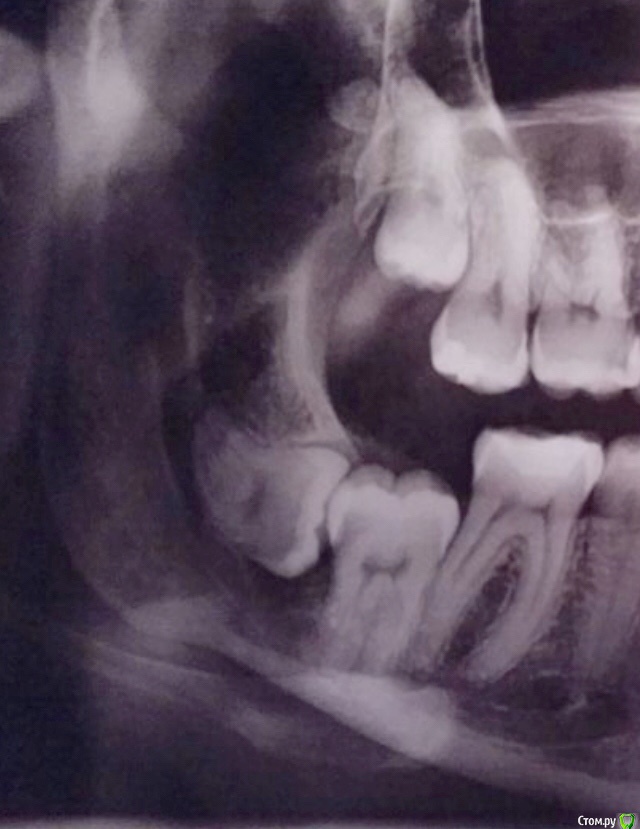

колесников Опубликовано 28 января, 2019 Поделиться Опубликовано 28 января, 2019 (изменено) Я работаю только прямым наконечником и только маленьким шариком, без охлаждения.Фрезы в угловой подключаю только если очень глубоко зуб.Долото никогда.Турбиной только зуб распиливаю.Линдеман на турбину это конечно круто))))) До луны досверлите. нука достаньте 48ой маленьким шариком . На снимке вот он ,а по факту: 5 мм десна,6 мм кость,2-3 мм капсула,после дистальный корень,далее перегородка и где то там на глубине 3см медиальный корень. Только линдеман на турбину . Изменено 28 января, 2019 пользователем колесников 4 Ссылка на комментарий